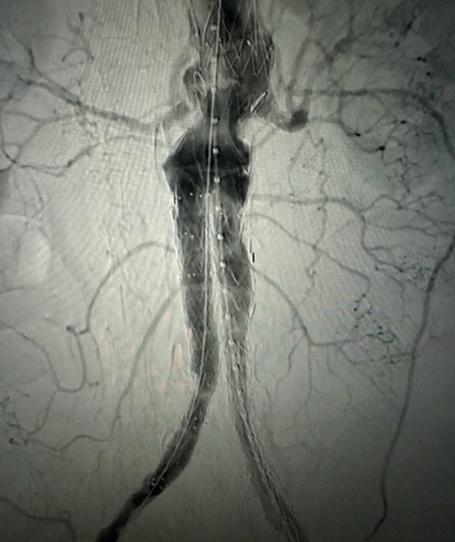

Case 1: The Shockwave L6 device in the setting of FEVAR and complex iliac stenosis

An 82-year-old man with a history of coronary artery disease (CAD), hypertension, hyperlipidemia, and peripheral arterial disease (PAD) presents with rest pain as well as

a large pararenal abdominal aortic aneurysm (AAA). His computed tomography angiography (CTA) revealed very dense and highly diseased iliac vessels with calcium deposition along most of the bilateral common iliac distribution.

The minimum luminal diameter (MLD) of the common iliac arteries measured roughly 4.5mm; however, the

healthy reference vessel diameter (RVD) was 9.5mm. He would require a fenestrated repair of the AAA along with complex iliac stenosis treatment, and extensive bilateral common femoral endarterectomies.

Further, we were concerned we would not be able to advance the 19F fenestrated graft. The endograft was prepared, and then both femoral arteries were exposed. We attempted delivery of the endograft via the right common iliac access. This failed. We then attempted delivery on the contralateral side. Despite multiple attempts, we made little progress. A 10x30mm Shockwave L 6 catheter was selected, and a total of 150 pulses were delivered to each iliac artery at just 4atm. This not only allowed for the delivery of our FEVAR graft but also the full unrestricted expansion of the endograft limbs in the common iliac arteries.

At the completion of the AAA, we took extra time to perform endarterectomies of the deep femoral arteries. His completion CT scan revealed a good seal of the AAA, patency of the renal fenestrations and unrestricted flow to the bilateral femoral arteries.

Figure 1. Pre-procdural CTA

Figure 4. Graft delivery

Figure 5. Final angiogram

Figure 3. Post-IVL angiogram

Figure 6. Post-procedural CTA